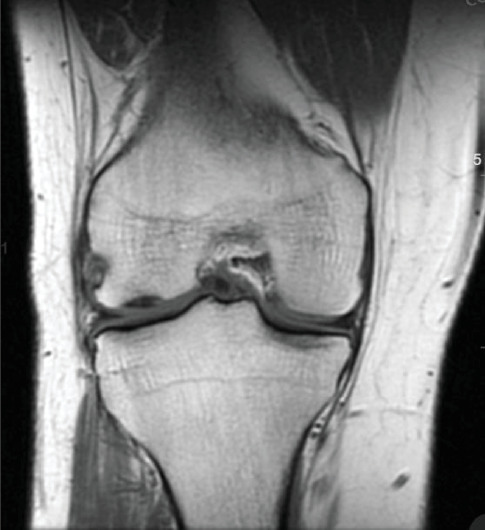

Purpose: Our work describes the use of matrix-induced autologous chondrocyte implantation (MACI) for a lateral tibial plateau osteochondral defect, in the setting of a concomitant meniscus repair and anterior cruciate ligament (ACL) reconstruction. To our knowledge, there is minimal research describing the application of MACI for cartilage defects of the tibial plateau, which brings about its own challenges. Methods: A 26-year-old male presented with lateral right knee pain and instability following a soccer injury. A bucket-handle lateral meniscus tear, 2 cm by 2 cm osteochondral defect of the lateral tibial plateau, and complete ACL tear were identified on magnetic resonance imaging (MRI). Our case vignette describes a two-stage MACI procedure for an osteochondral defect of the lateral tibial plateau with concurrent all-inside meniscus repair and ACL reconstruction using bone-patellar tendon-bone (BTB) autograft. Results: Follow up period was 20 months with excellent patient satisfaction and resolution of pain. Outcome measures (International Knee Documentation Committee (IKDC)) and Knee Injury and Osteoarthritis Outcome Score (KOOS) returned to preinjury levels at 8.5 months. Return to sport was achieved at 10 months postoperatively. Conclusion: The miniopen MACI procedure provides a logistically reasonable technique mitigating the anatomic challenges of tibial plateau osteochondral defects and potentially providing improved long-term outcomes. It is our hope that this work will contribute to the current understanding of the treatment options for osteochondral defects of the tibial plateau.

Abstract Image